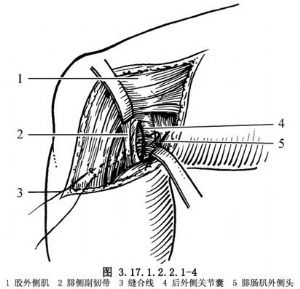

如半月板和交叉韌帶有損傷,儘可能予以修補,然後再自後側開始修補外側結構。①如有後外側關節囊撕脫,將其牽到脛骨關節面下方,用圓針引絲線穿過脛骨關節面下的鑽孔,由前到後縫合固定在脛骨上(圖3.17.1.2.2.1-4)。固定前將脛骨附着部的骨表面弄毛糙,或用骨刀做一新鮮骨創面,以保證後外側關節囊的固定。②有膕肌腱撕裂者,按損傷類型採用不同的方法。股骨附着部的膕肌腱撕裂,常伴有外側副韌帶自股骨上撕脫,可採用Bunnell縫合,通過股骨的鑽孔,捆紮在股骨內上髁的骨面上(圖3.17.1.2.2.1-5)。膕肌腱本身撕裂,將兩端用Bunnell縫合(圖3.17.1.2.2.1-6)。撕裂在肌肉內或肌腱連接部,用Bunnell縫合通過脛骨前外側近端Gerdg結節的骨孔,將肌腱附着到脛骨的後面(圖3.17.1.2.2.1-7)。③修補外側副韌帶。對外側副韌帶的撕裂先明確撕裂的部位,對股骨附着部的撕脫可採用U形釘、螺釘固定,或將斷端用Bunnell縫合,通過股骨的鑽孔捆紮在股骨內上髁上。外側副韌帶從腓骨頂點撕裂則伴有股二頭肌腱、弓狀韌帶及腓側副韌帶附着點的複合撕脫,應一併修復,在腓骨頭穿孔,粗線縫合固定。伴有骨片撕脫,可用1枚螺釘或交叉克氏針固定骨片(圖3.17.1.2.2.1-8)。如爲韌帶本身的撕裂,找出兩斷端拉緊後屈膝30°位,用不吸收的絲線對端或重疊縫合(圖3.17.1.2.2.1-9)。並將外側緣向前推進,縫合在外側正中關節囊的後緣和外側副韌帶的後緣。還可應用股二頭肌腱、腓腸肌腱和髂脛束加強修補。